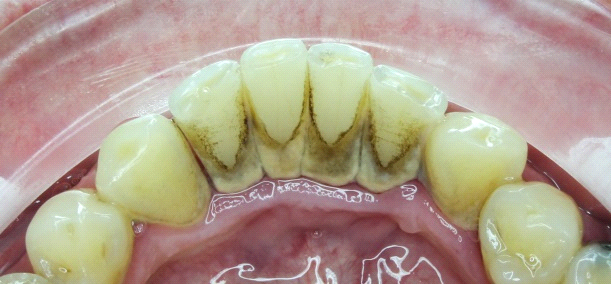

Dentálna hygienička sa potom pustí do čistenia vášho úsmevu. Pomocou ultrazvuku odstráni zubný kameň, ktorý vzniká mineralizovaním zubného povlaku a časom sa môže zmeniť na zubný kaz. Celý proces funguje tak, že ultrazvuk naruší priľnavosť zubného kameňa a ten odpadne. Ak je potrebné odstrániť ho mechanicky, použijú sa škrabky alebo kyrety.

Zubný kameň sa však nenachádza len na zuboch, ale aj pod ďasnom. Síce ho nevidno, ale to neznamená, že nie je škodlivý. Práve naopak, môže narobiť veľa škody! Na dentálnej hygiene sa ho ľahko zbavíte napríklad pomocou laseru.

Na odstránenie povlaku a zafarbenia (napr. z kávy, cigariet, jedál…) použije dentálna hygienička kefky, leštiace pasty či “air flow”. Tento prístroj (po slovensky “pieskovač”) krásne vyleští a vyčistí vaše zuby prúdom vzduchu, vody a jemného prášku.